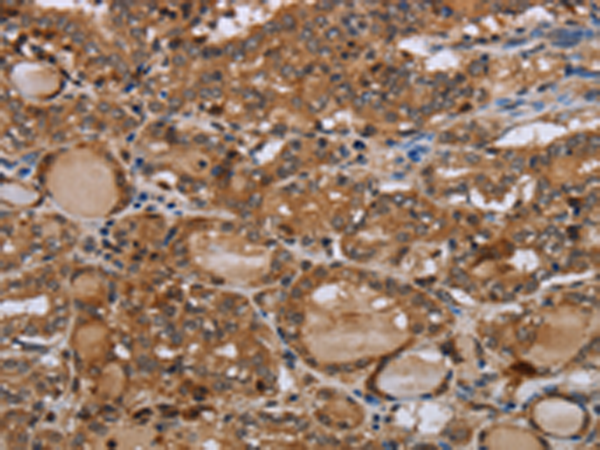

分类: 科研抗体货号: P05124别名: OT-R应用: IHC反应种属: Human, Mouse, Rat